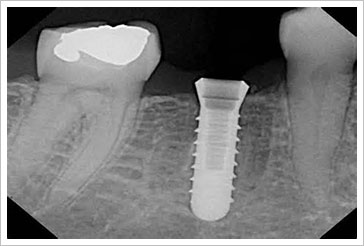

牙根種植體是一個以鈦金屬製成的小「錨」植入顎骨,以取代失去的牙根。經過骨整合,與環繞植體的骨頭癒合之後,用替代的人造牙固定於植體的頂端。如此新造牙齒無論在外觀、感覺及功能上,都與您原本的牙齒相似。如果不是很清楚了解其中的異同,由下面這張比原牙齒及植牙區分比較圖,我們可以很明顯的看出來植牙物質的部位,跟我們原本的牙齒之間的比照位置以及差異。如表面仿真的定制牙冠以及取代牙根的植體。

在局部或全身麻醉時,牙科醫師將人工種植體放入顎骨。接下來的數個月,骨頭將會癒合到植體的表面,達到骨整合。然後依個人狀況,在牙齦進行一個小手術,以便人造假牙鎖扣於人工牙根上。

植牙可說是一項非常精細的醫療技術,正統的植牙是將類似牙根的長柱體,經由手術旋入牙床骨內,如果施行上顎竇提高術,骨床整合依其手術複雜度,最好需等待4~12個月,下顎至少2~6個月,齒槽骨才能與人工植體緊密的結合,直到骨整合完畢後再進行二接手術,將露出的人工植牙再與假牙根連結縫合完成,再等1至2個月讓牙齦癒合完成,就可以重建假牙,擁有與真牙般自然的贗復體。